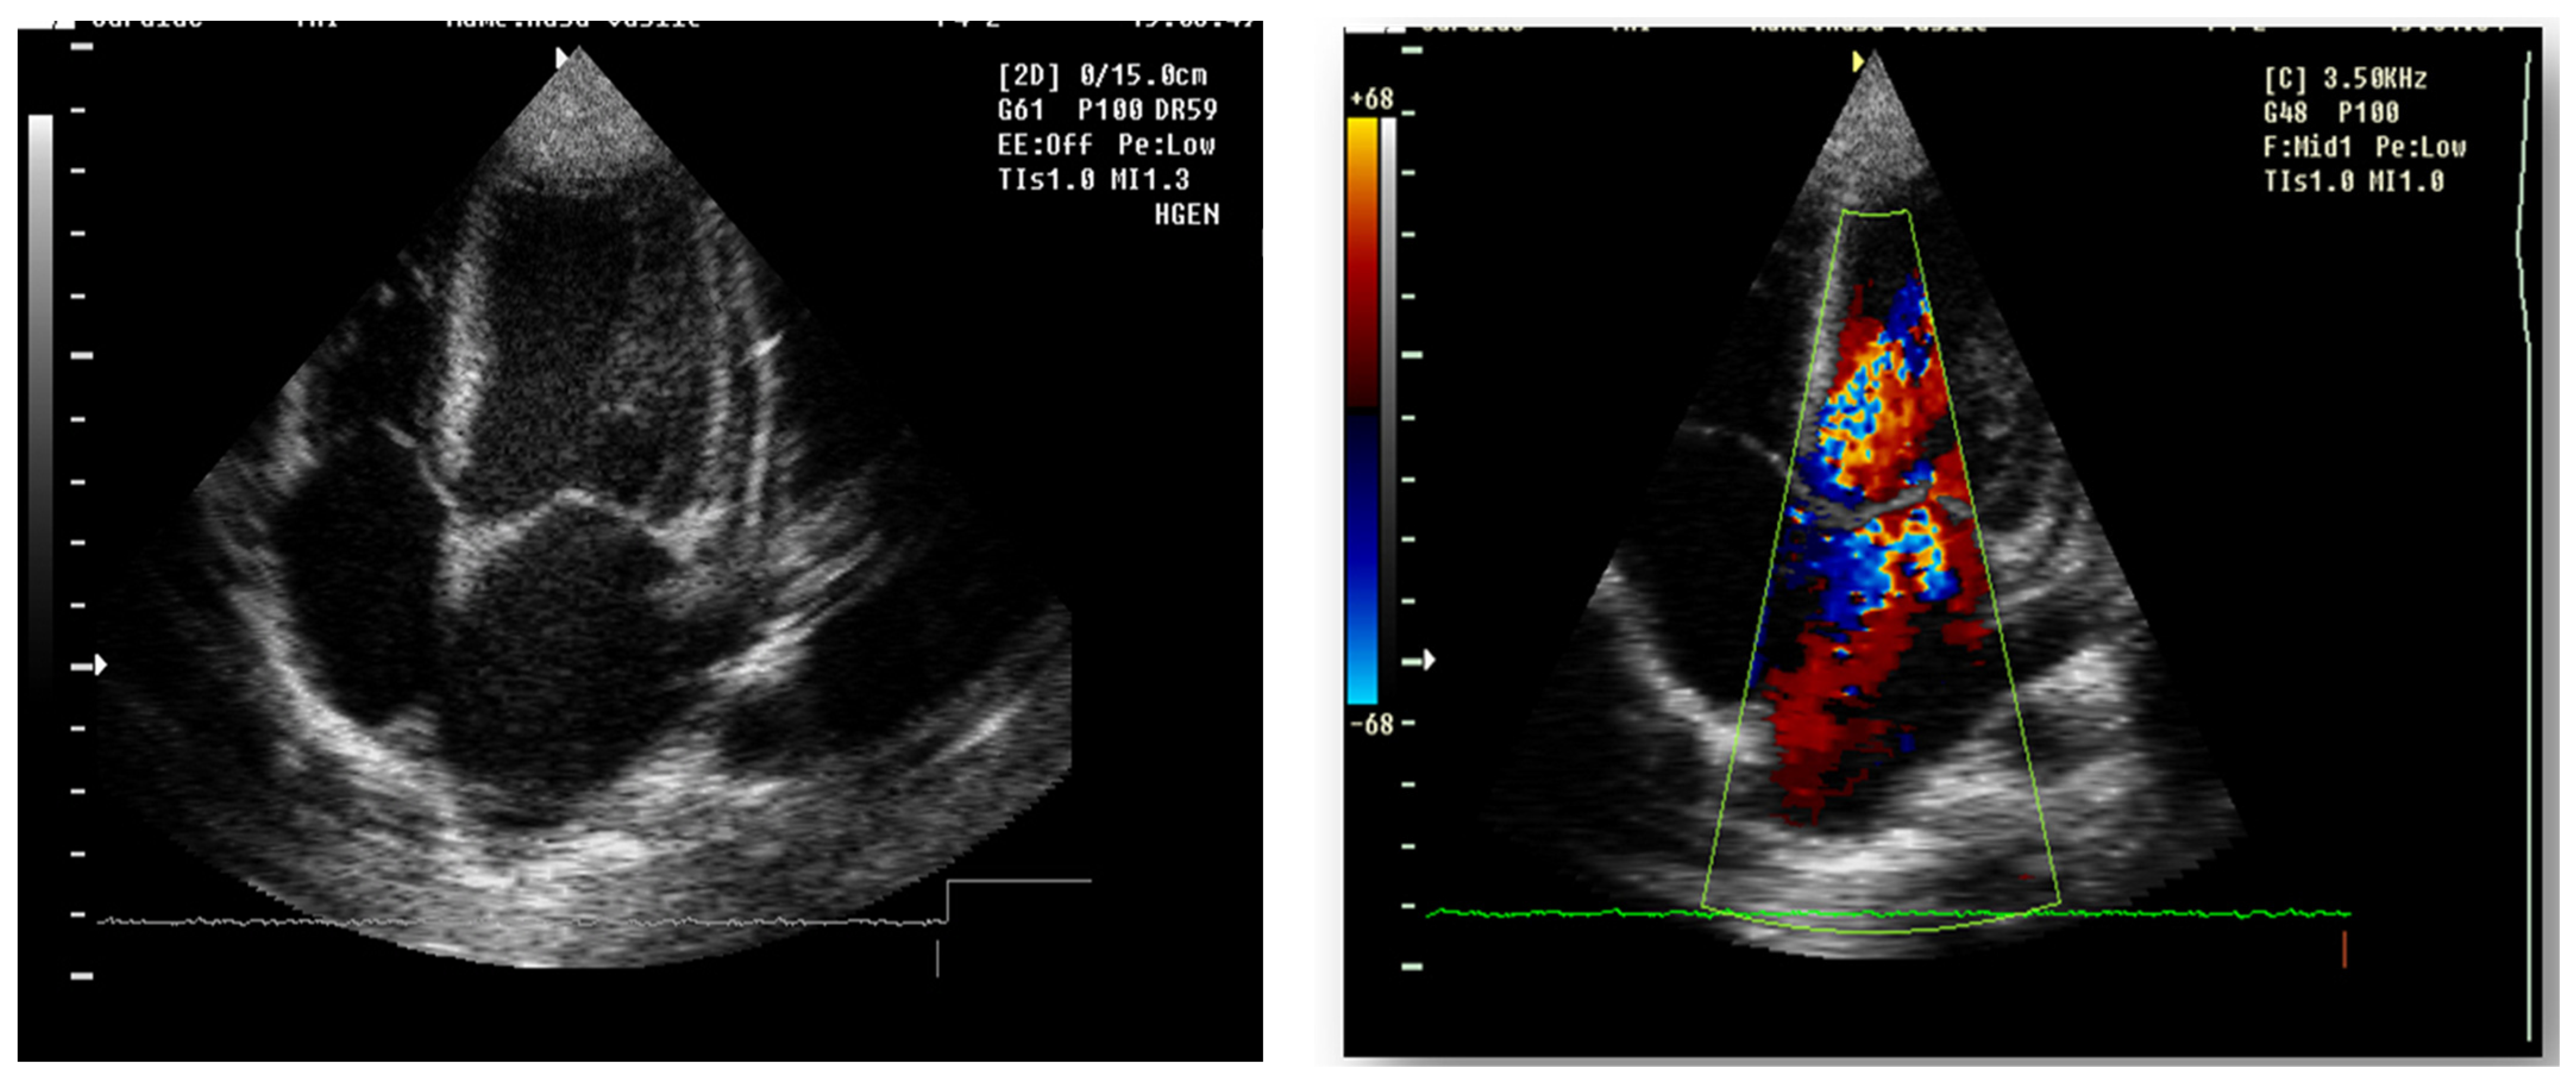

Echocardiography (Figure 9)

mitral insufficiency second degree

aortic insufficiency first degree

tricuspid insufficiency first degree

dilatation of the left heart

ejection fraction 50%

fine pericardial reaction, 3 mm

Figure 9. Echocardiography 4 chamber transthoracic apical view: echodense mitral and aortic valve, II-degree mitral regurgitation and I degree aortic regurgitation, pulmonary and tricuspid valve echodense, with I degree regurgitation. Left atrium and Left ventricle dilatation, normal kinetics, EF 70%, inferior vena cave not dilated, with inspiratory collapse, E/A > 2.

Forty-six days after admission, the patient suddenly complained one morning of epigastric pains, nausea and palmo-plantar burning, associated with a hypertensive episode (BP 180/110 mmHg), for which reason a hemodialysis session was performed urgently, extracurricular. In the same evening, at a BP value of 160/100 mmHg, at rest, the patient presented a sudden and severe worsening of the general condition, dyspnea with orthopnea, intense wheezing, SaO2 89–91%, tachycardia 140/min, subcrepitants disseminated on both lung areas. The suspicion of cardiogenic acute pulmonary edema was confirmed by imaging (chest X-ray—Figure 7, Table 1). Electrocardiographic evaluation (Figure 8, Table 1) revealed subendocardial myocardial ischemia, and echocardiography revealed acute dilation of the left heart, as well as a fine pericardial reaction, 3 mm, without signs of cardiac tamponade (Figure 9, Table 1). At that moment, we made 2-h ultrafiltration, during which the signs of acute pulmonary edema subsided. After 60 min an increase in blood pressure up to 160/120 mmHg is noted, with the maintenance of negative T waves on the monitor. Hemodialysis was stopped and iv Nicardipin was administered, with good results.

The major sign of cardiac involvement in Fabry disease is left ventricular hypertrophy, but conduction disturbances such as short PR interval (due to accelerated conduction in the absence of the accessory pathway) and rhythm disturbances such as sinus bradycardia have also been reported. Cardiac ultrasound and ECG are indicated at baseline and at all follow-up visits. Holter testing is recommended only if indicated by symptoms, as severe arrhythmias are not usually encountered in early childhood [18]. In our case, the boy presented dilatation of the left cavities with secondary mitral and aortic regurgitation from the beginning. This could not be attributed only to hypertension secondary to chronic kidney disease, because it regressed after the initiation of enzyme replacement therapy. During the follow-up, he did not present any rhythm or conduction disorders, but the phenomena of myocardial ischemia were observed in the context of hemodialysis, requiring a change in the method of renal replacement.